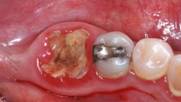

Сложное удаление зуба

это нестандартная трудоемкая операция по извлечению зуба в условиях осложненного доступа к нему. Зачастую сложное удаление применительно к ретенированным зубам мудрости и двухкорневым зубам, в случае, если зуб сильно разрушен или расположен под уровнем десны.  В ходе такой операции производится разрез десны и надкостницы, для формирования доступа к корню зуба, возможно удаление определенного количества ткани вокруг зуба или извлечение зуба по частям.

Если остался кусочек зуба после удаления существует два пути развития процесса:

• В первом случае, если фрагмент или отломок инфицирован кариозным процессом или его осложнениями, то неизбежно наступление осложнения воспалительного характера с необходимостью дальнейшего хирургического лечения в форме кюретажа лунки и удаления причинного объекта.